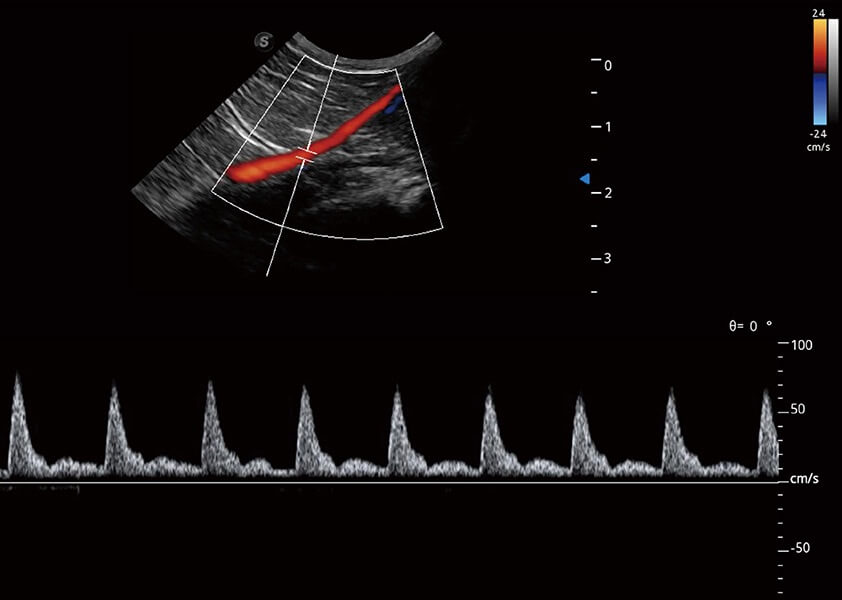

优异的基础图像

(猫)髂动脉血流频谱